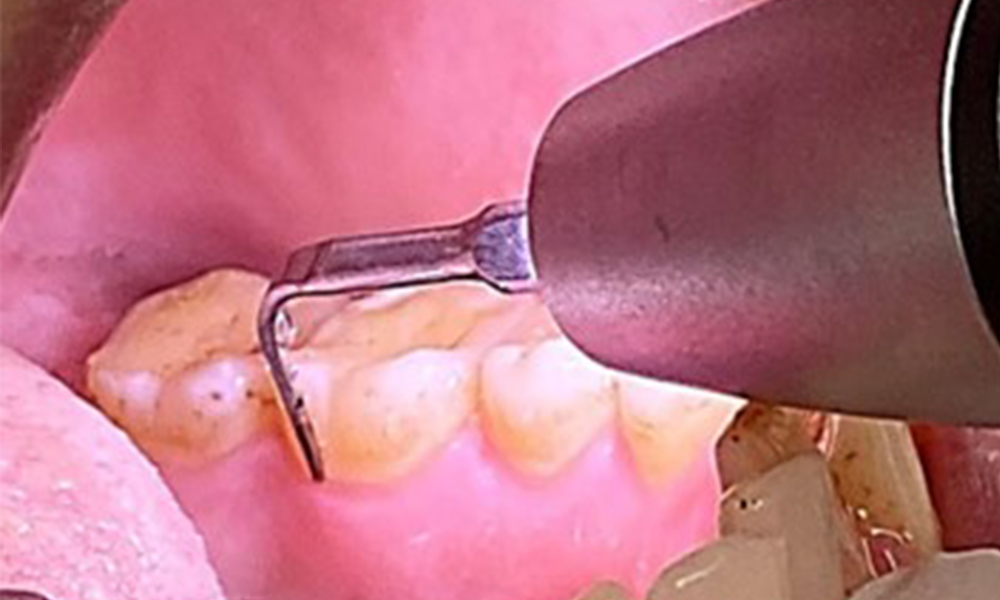

The objective would be to control disease risk by removing supragingival and subgingival biofilm. The instruments can be selected based on patient needs. First, calculus and any concretions must be removed using ultrasonic and/or manual instruments (Fig. 10).

Use of a piezo-driven ultrasonic device in the lingual area near 36 (Proxeo Ultra, W&H, shown here)

Fig. 10 Use of a piezo-driven ultrasonic device in the lingual area near 36 (Proxeo Ultra, W&H, shown here), © Dr R. Krapf